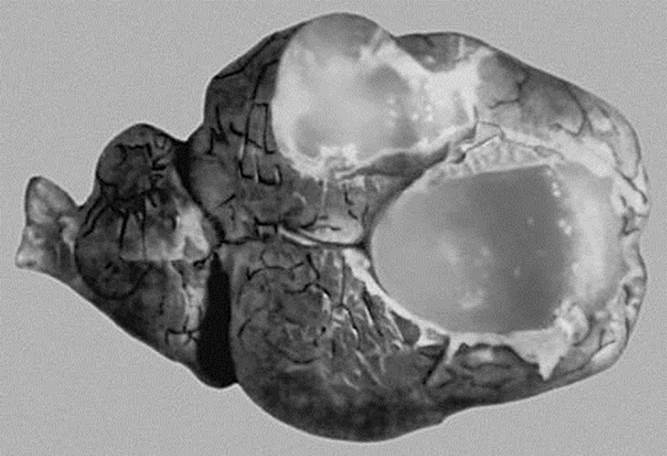

ленточный червь семейства тениид (Teniidae). Тело длиной 4—10 см, шириной до 5 мм, состоит из 200—250 члеников. На головке 4 присоски и хоботок с 22—32 крючьями, расположенными в 2 ряда (рис. 1). Половозрелый М. о. паразитирует в кишечнике собак и других псовых. Последние членики тела М. о., содержащие в матках по 20—60 тыс. яиц с развивающимися личинками — Онкосферами, созревая, отпадают и выделяются с калом собак. В пищеварительном тракте промежуточного хозяина — овцы, реже другого животного или человека — онкосфера выходит из яйца, проникает в кровь и с её током достигает мозга, где превращается в одну из личиночных форм тениид — ценур (рис. 2), вызывая тяжёлое заболевание — ценуроз (См. Ценурозы). Собаки заражаются, поедая мозг болевших овец.

Рис. 2. Мозг овцы, пораженной ценуром: а — ценурозные пузыри с беловатыми головками червя.